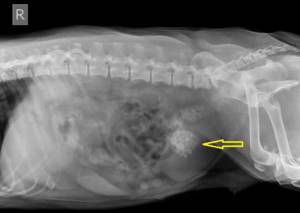

Диагноз мочекаменная болезнь ставится на основании клинических признаков лабораторной и инструментальной диагностики. Несомненно, первым из методов диагностики является общий анализ мочи. Главный акцент при этом ставится на изучение солевого осадка: оксалаты, струвиты (трипельфосфаты), ураты. Точность при определении вида кристаллов очень важна, т.к. в дальнейшем будет учитываться при назначении лечения. Дополнительные сведения о месте локализации, форме, размере и количестве конкрементов могут быть получены с помощью рентгенологического и ультразвукового исследования (УЗИ). При необходимости учитываются результаты биохимического анализа крови.

Рентгенограмма: собака, 10 лет, уроцистолитиаз (камни в мочевом пузыре)